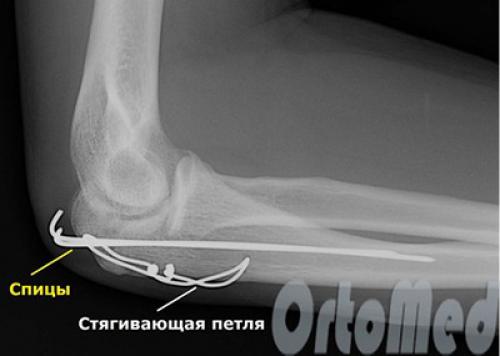

Хирургическое лечение в нашей клинике

Перелом локтевого отростка, имеющий выраженное смещение осколков, требует обязательного оперативного вмешательства хирурга-травматолога. Иначе предплечье не будет полностью разгибаться, это серьезное нарушение функции верхней конечности. Успех операции зависит от точного сопоставления костных отломков и их фиксации в правильном анатомическом положении. А в дальнейшем успех зависит от правильной разработки локтевого сустава.

Наилучшим методом лечения внутрисуставного перелома локтевого отростка, позволяющим сохранить движения в суставе – это остеосинтез (устранение смещения и фиксация отломков металлоконструкцией). Операцию выполняют сразу после поступления пациента. Это ускорит реабилитацию и позволит сохранить полный объем движений в локтевом суставе. Локтевой сустав очень капризный в плане реабилитации. Если иммобилизация продолжается 4 недели и более, то практически во всех случаях у взрослых пациентов развивается контрактура.то есть движения ограничены на всю жизнь. Если перелом локтевого отростка произошел одним фрагментом, то возможна классическая операция, одна из самых простых и надежных методик - остеосинтез локтевого отростка по Веберу. Выполняется она при помощи двух титановых спиц и титановой проволоки.